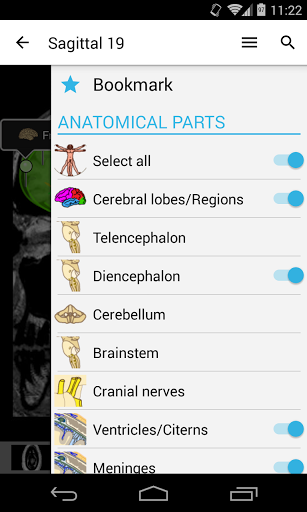

e-Anatomy memiliki lebih dari 26.000 gambar yang berisi serangkaian gambar dalam tampilan aksial, koronal, dan sagital serta radiografi, angiografi, gambar diseksi, bagan anatomi, dan ilustrasi. Semua gambar medis diberi label dengan cermat, lebih dari 967.000 label tersedia dalam 12 bahasa termasuk Terminologia Anatomica Latin.

- Pilih label anatomi berdasarkan kategori